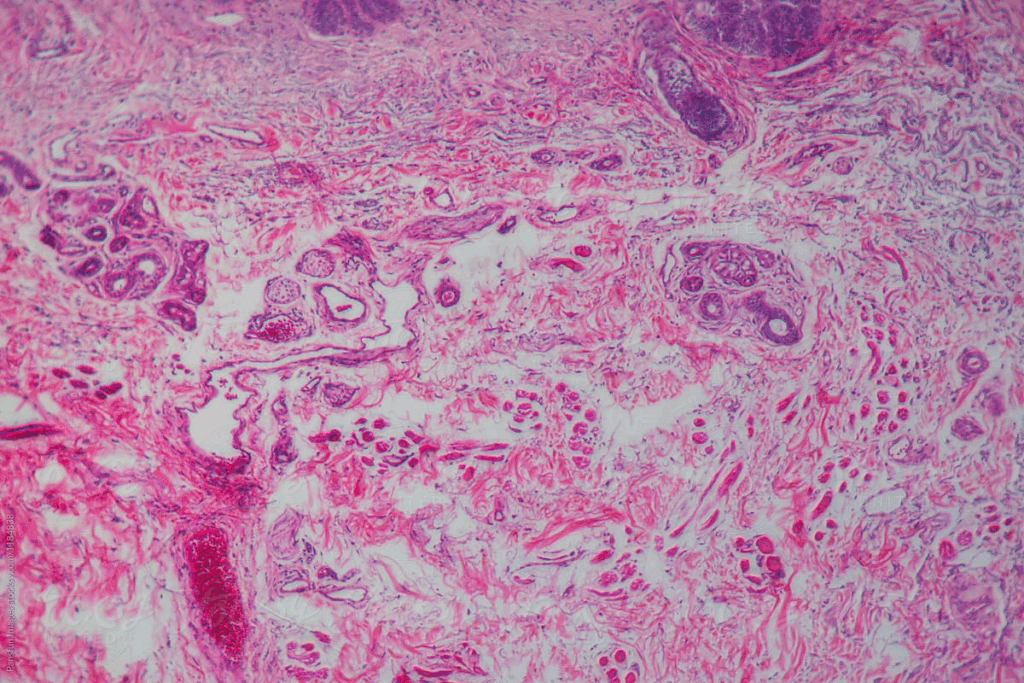

Basal Cell Cancer Pictures: Identifying Different Presentations

Basal cell carcinoma shows up in many ways, making it key to know its forms. It’s the most common skin cancer. It can look like a firm, round growth, a circle that dips in the middle, or a scaly spot.

Images of Skin Cancer on Face and Scalp

It often pops up on sun-exposed spots like the face and scalp. On the face, it might look like a pearly or waxy bump with blood vessels. On the scalp, it’s a firm, raised lesion that bleeds easily.

Skin Cancer on Fingers and Arms

Basal cell carcinoma can also show up on fingers and arms, though it’s less common. On fingers, it’s a small, painless nodule. On arms, it’s a flat, firm area that’s pale or red.

Identifying Basal Cell Carcinoma on Trunk and Back

On the trunk and back, it’s harder to spot because of the bigger area and different skin tones. It might look like a scaly patch or a circle-shaped lesion with a depressed center.

Knowing these different looks helps us spot basal cell carcinoma early. This makes it easier to treat.